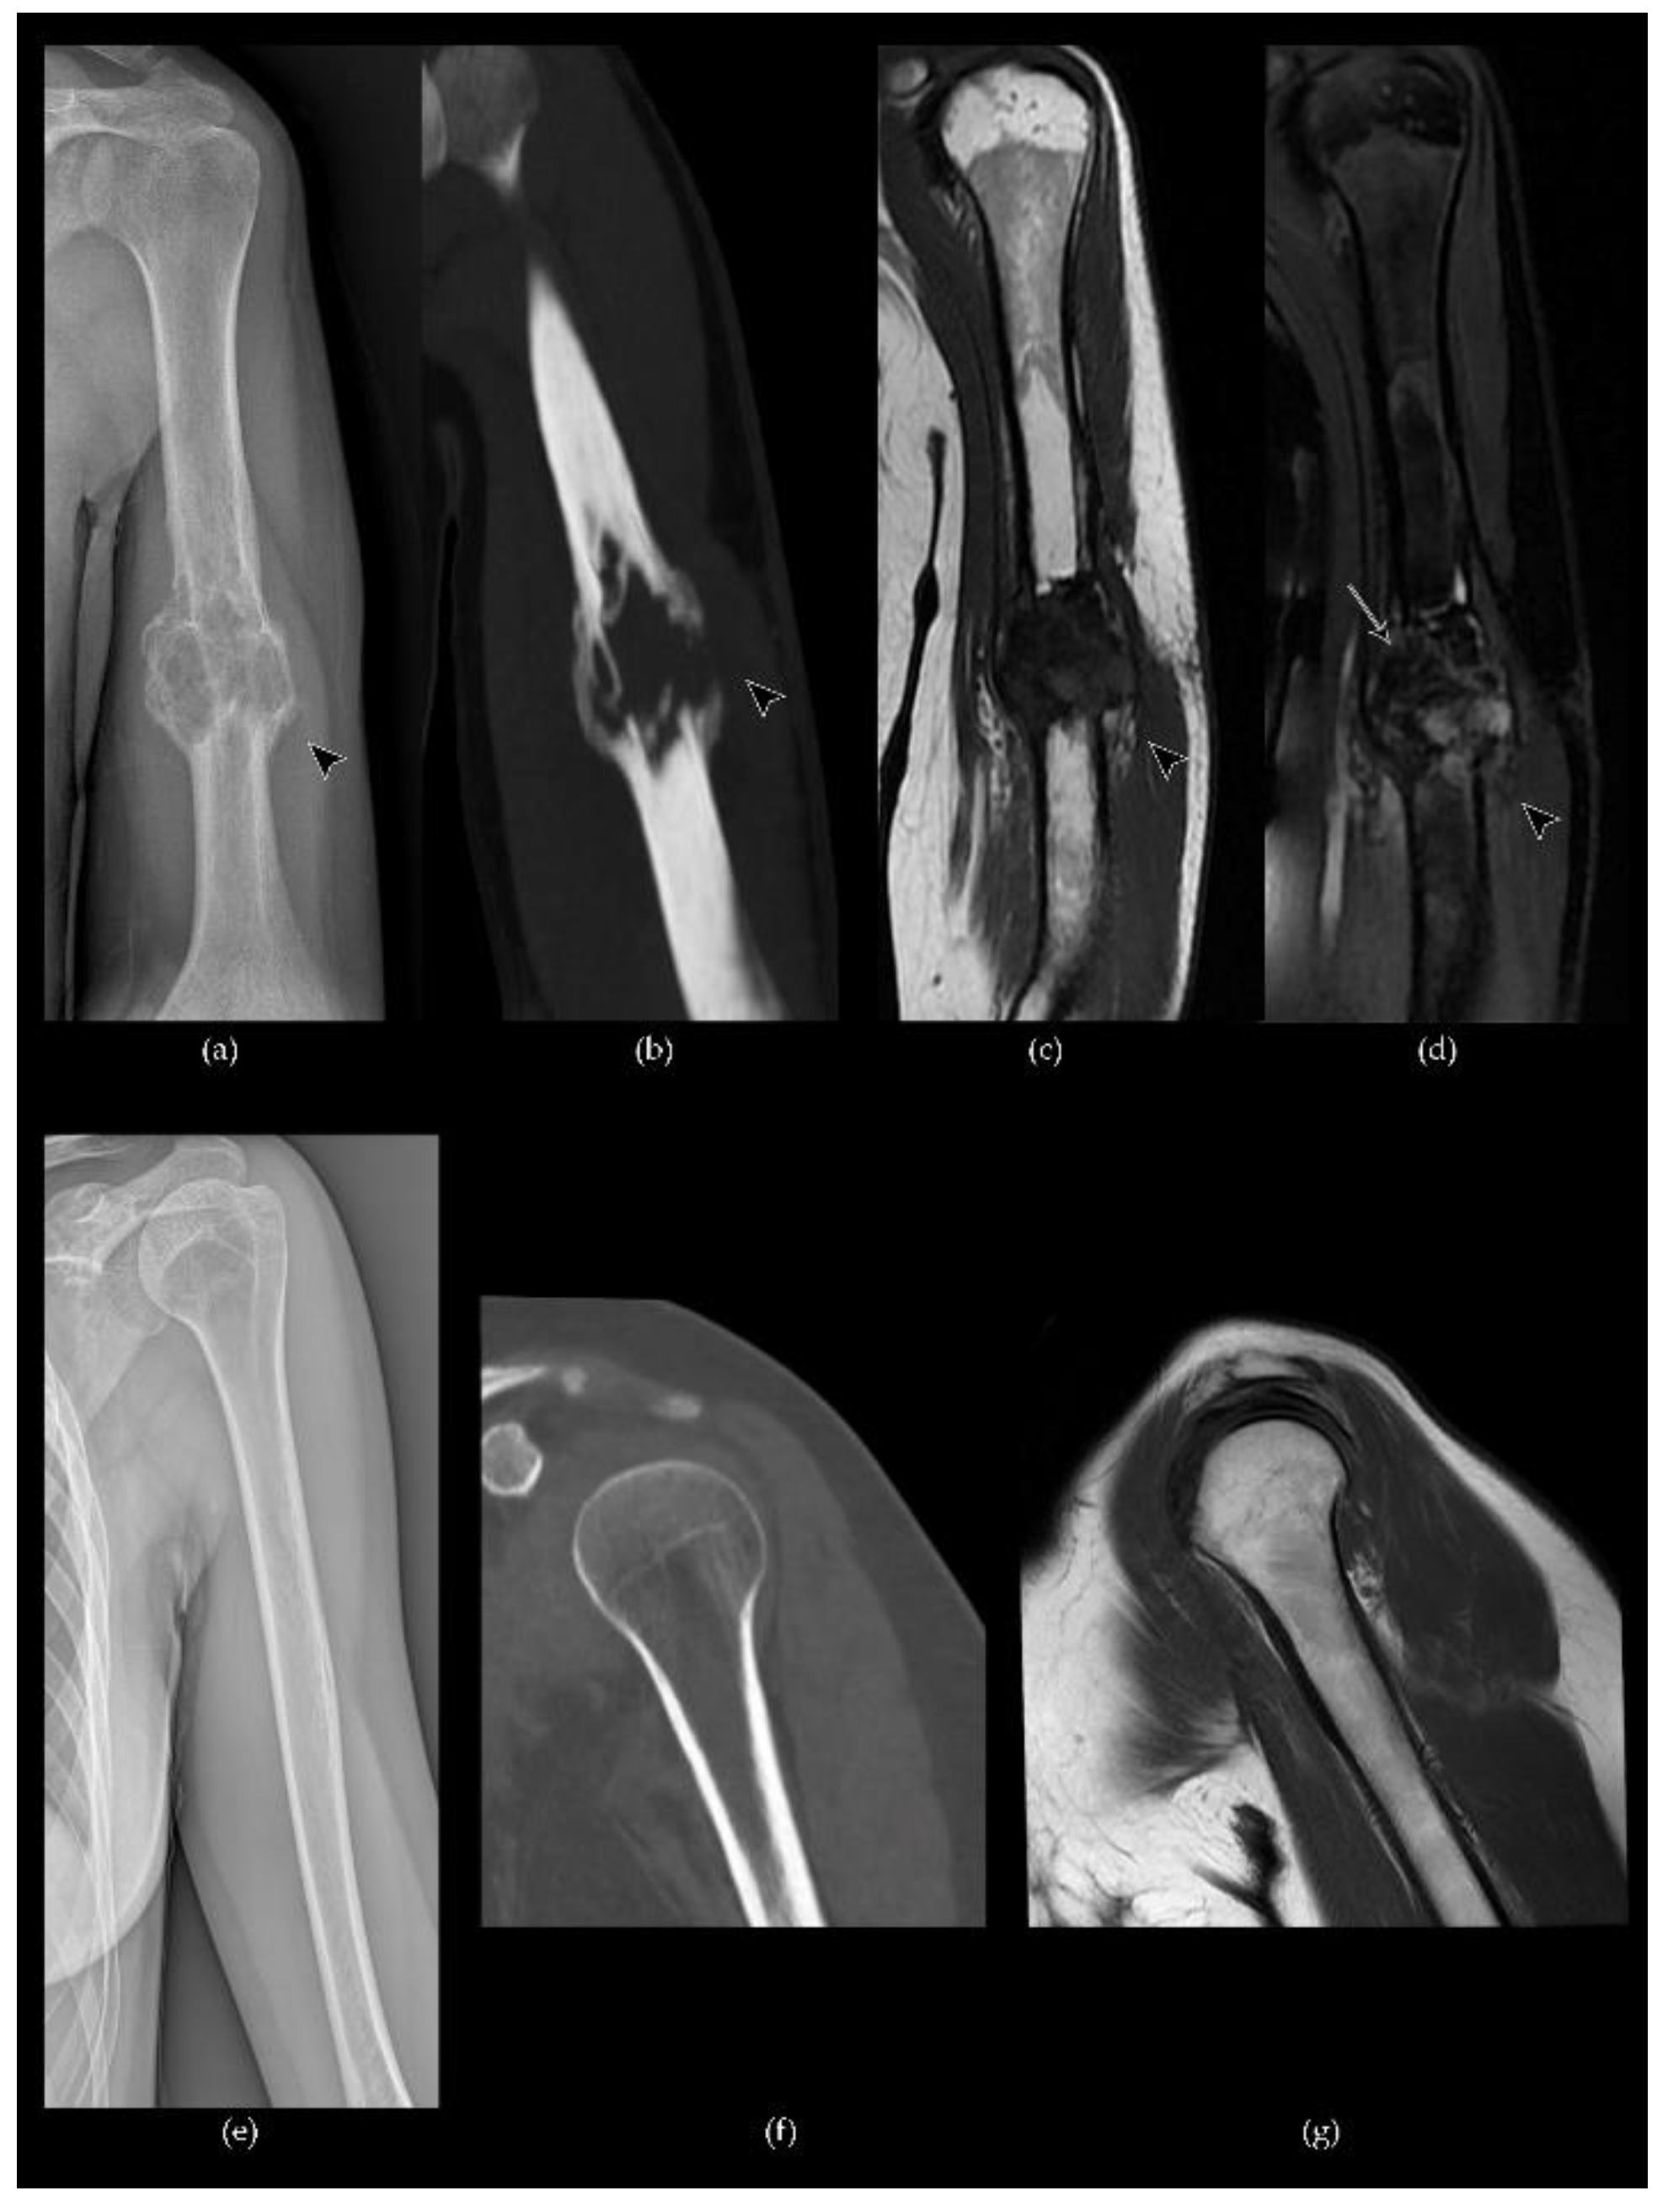

- Murphey, M.D.; Nomikos, G.C.; Flemming, D.J.; Gannon, F.H.; Temple, H.T.; Kransdorf, M.J. From the archives of the AFIP. Imaging of giant cell tumor and giant cell reparative granuloma of bone: Radiologie-pathologic correlation. Radiographics 2001, 21, 1283–1309. [Google Scholar] [CrossRef] [PubMed]

- Chakarun, C.J.; Forrester, D.M.; Gottsegen, C.J.; Patel, D.B.; White, E.A.; Matcuk, G.R. Giant cell tumor of bone: Review, mimics, and new developments in treatment. Radiographics 2013, 33, 197–211. [Google Scholar] [CrossRef]

- Pereira, H.M.; Marchiori, E.; Severo, A. Magnetic resonance imaging aspects of giant-cell tumours of bone. J. Med. Imaging Radiat. Oncol. 2014, 58, 674–678. [Google Scholar] [CrossRef]

- Aoki, J.; Tanikawa, H.; Ishii, K.; Seo, G.S.; Karakida, O.; Sone, S.; Ichikawa, T.; Kachi, K. MR findings indicative of hemosiderin in giant-cell tumor of bone: Frequency, cause, and diagnostic significance. AJR Am. J. Roentgenol. 1996, 166, 145–148. [Google Scholar] [CrossRef]

- Nishibori, H.; Kato, H.; Kawaguchi, M.; Nagano, A.; Matsuo, M. T2*-weighted MR imaging findings of giant cell tumors of bone: Radiological–pathological correlation. Jpn. J. Radiol. 2019, 37, 473–480. [Google Scholar] [CrossRef]

- Baumgartner, K.; Haap, M.; Bösmüller, H.; Horger, M. Imaging of giant cell tumors of the bone, RoFo Fortschritte Auf Dem Gebiet Der Rontgenstrahlen Und Der Bildgeb. Verfahren 2020, 193. [Google Scholar] [CrossRef]